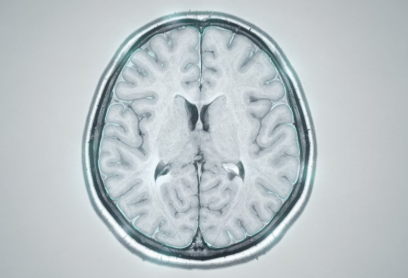

중풍은 흔히 뇌졸중이라고 불리는 질환으로, 뇌혈관이 막히거나 터지면서 발생합니다. 한 번 발생하면 후유증이 크고, 생명까지 위협할 수 있기 때문에 사전 신호를 알아차리는 것이 무엇보다 중요합니다.

많은 사람들이 “갑자기 쓰러지는 병”이라고 생각하지만, 실제로는 그 전에 다양한 전조증상이 나타나는 경우가 많습니다. 문제는 이 신호들이 짧게 나타났다 사라지기 때문에 쉽게 무시된다는 점입니다.